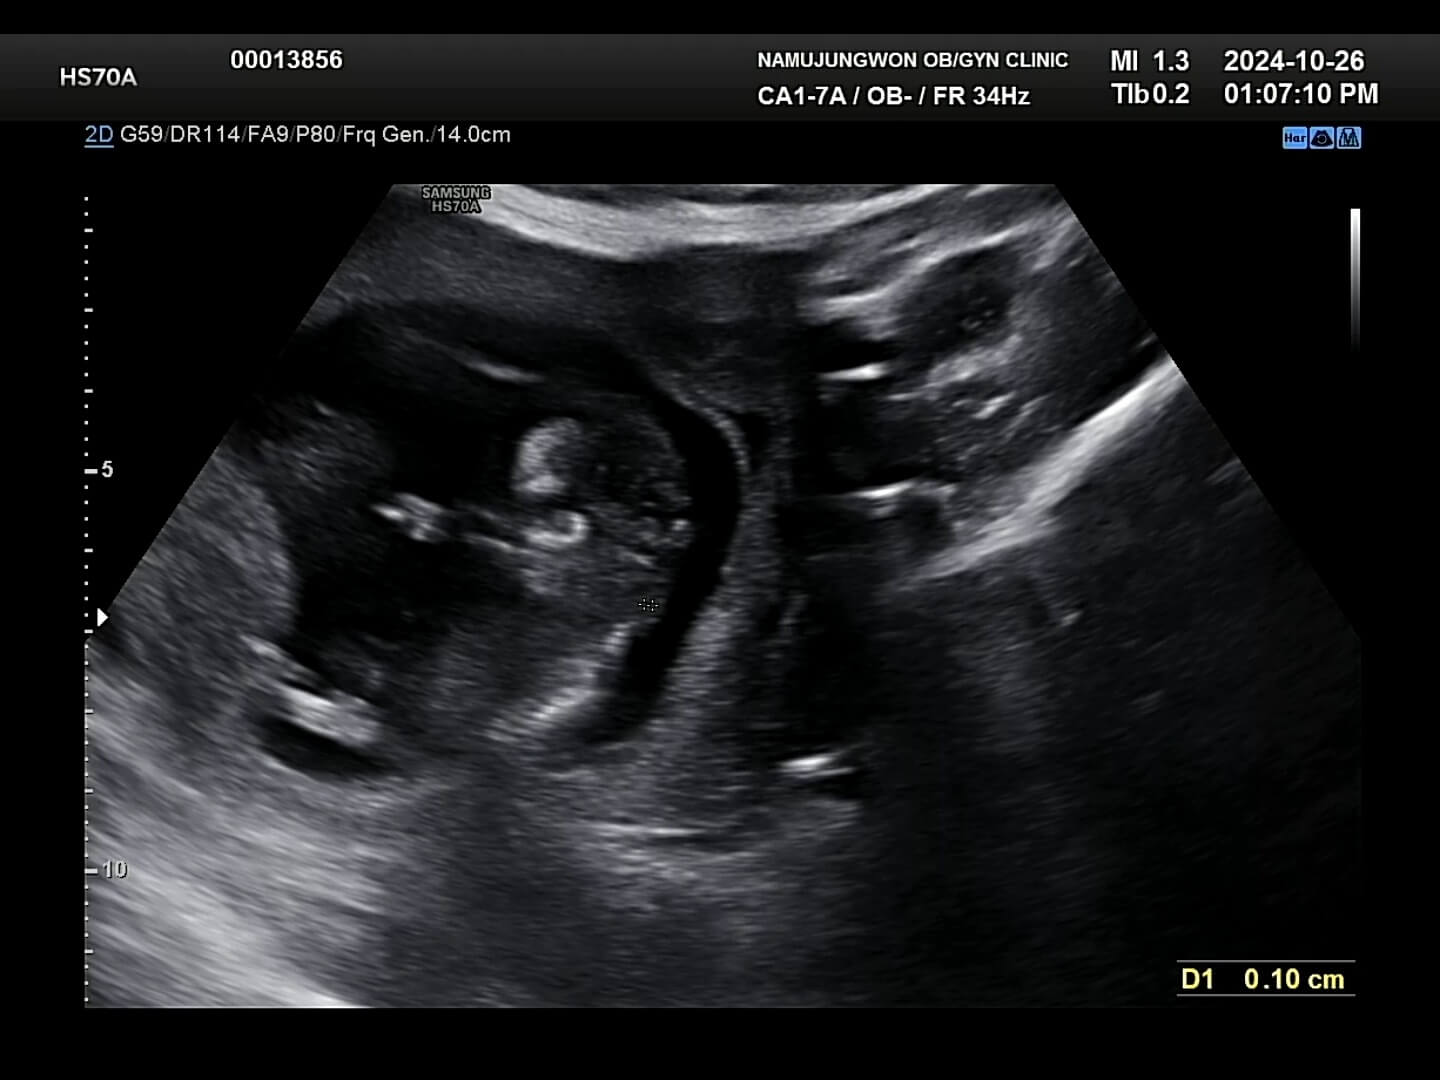

8주차-초음파사진 8주에서 9주 정도에는 초음파 사진을 보시면 아시겠지만, 손과 발이 나와서 마치 하리보 젤리의 젤리곰 같은 배아를 보실 수 있습니다. 거의 1~2주일만에 이렇게 큰 모습을 보니까 너무너무 귀여웠습니다. 2주만에 본 꾸미는 젤리곰이 되어서 꿈틀꿈틀 춤을 추고 있었고, 마치 짧고 귀여운 팔로 '엄마, 안녕!' 하는 기분이었어요.